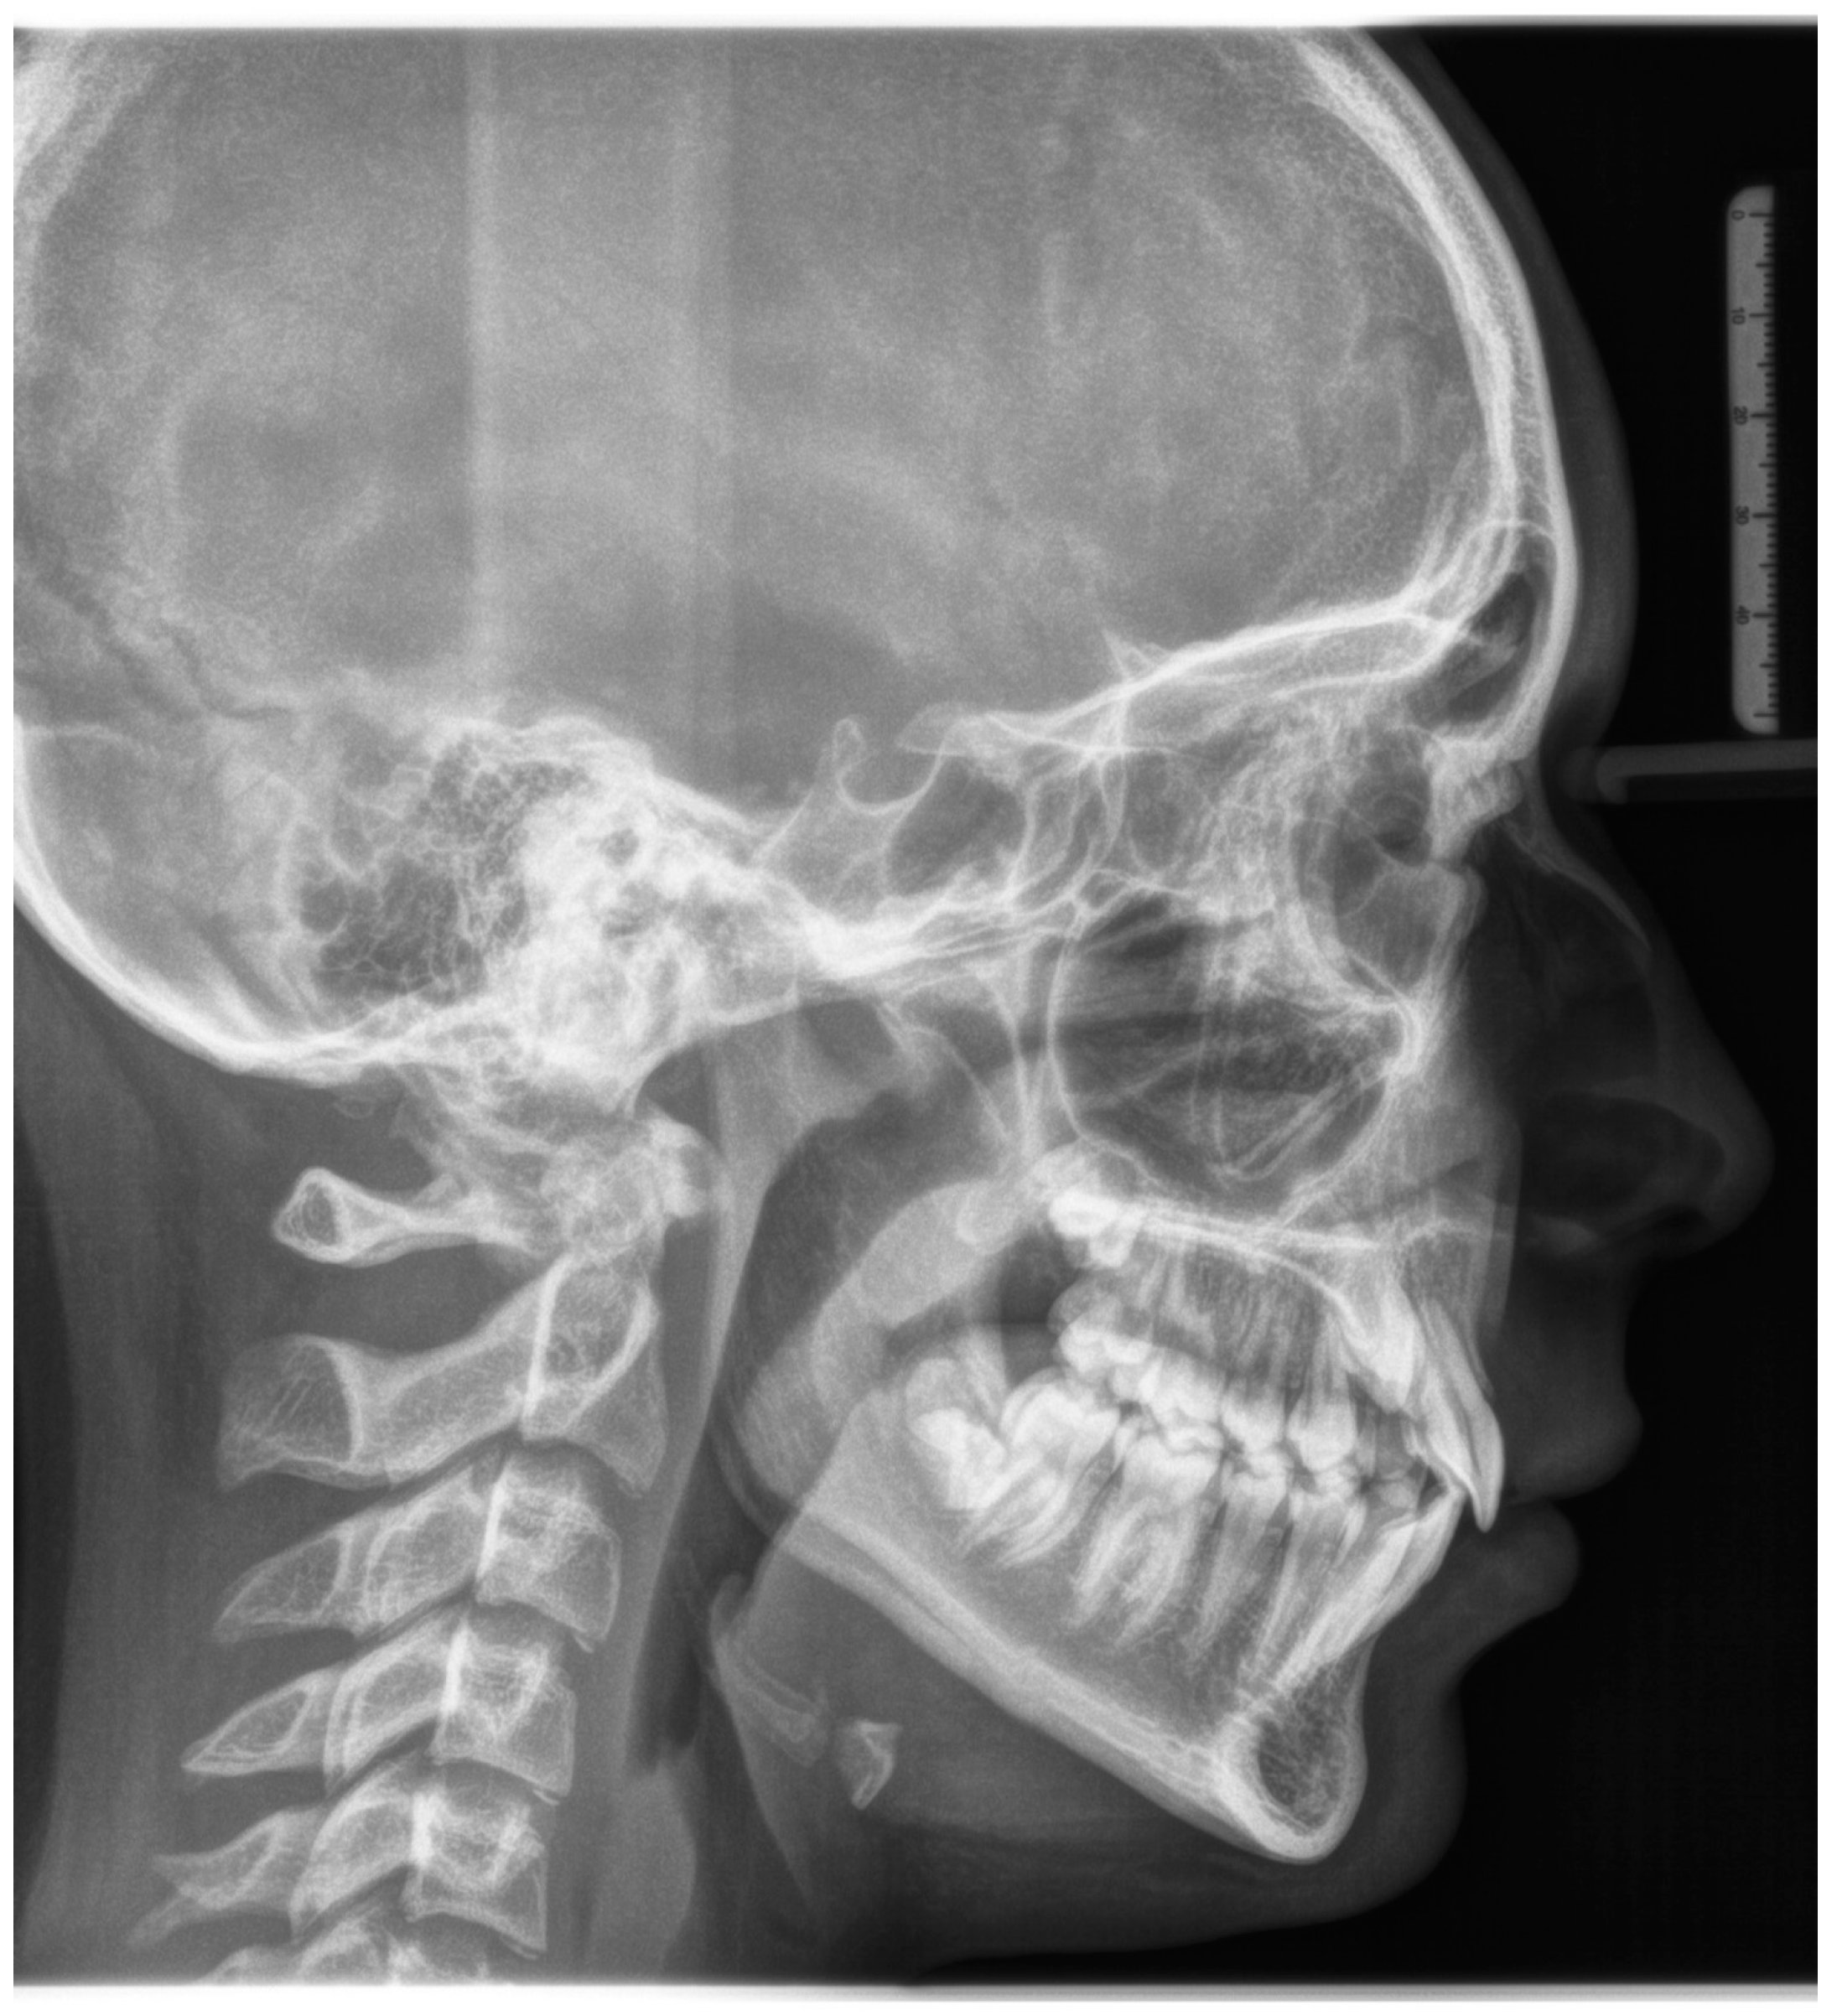

2. Case Report

2.1. Treatment Progress